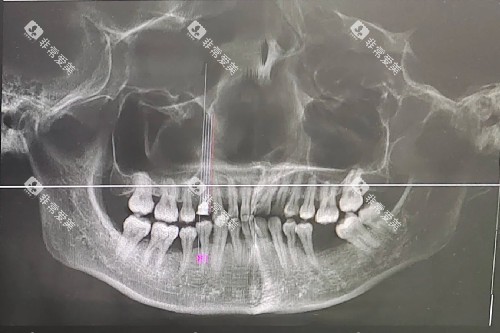

骨吸收率是衡量种植牙质量的一个重要指标。

大清西格种植牙的一大显著优势就是骨吸收率非常低。这意味着在种植牙植入后,牙槽骨能够更好地与种植体结合,保持稳定的状态。

较低的骨吸收率可以有效减少种植体周围骨组织的流失,延长种植体的使用寿命。

对于患者来说,这就意味着种植牙能够在口腔内长期稳定地发挥功能,减少了后期出现松动、脱落等问题的风险,提高了种植牙的成功概率和使用结果。